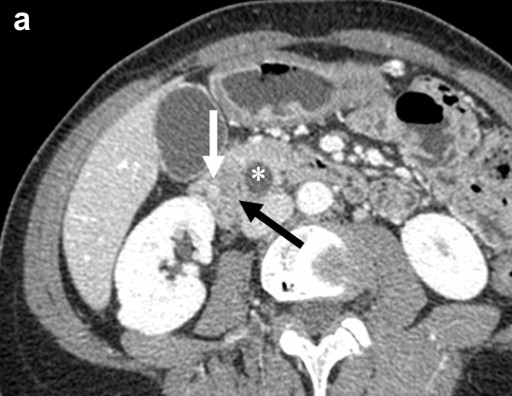

A 49-year-old woman with neurofibromatosis type 1 presented with atypical abdominal pain. Endoscopic examination revealed a duodenal villous tumor involving the ampulla of Vater. A CT scan showed a 2 cm ampullary tumor with stenoses of both the distal common bile duct and the main pancreatic duct (Figure 1a). Neither lymph node nor distant metastases were found. Endoscopic ultrasound identified an ampullary tumor with some papillary projections in the juxta-ampullary main pancreatic duct and a slight upstream biliary dilatation. Analysis of the bioptic specimens revealed a high grade tubulo-villous adenoma without invasive adenocarcinoma.

Figure 1. a. CT-scan slice at the level of the ampulla, obtained during the arterial phase after an intravenous injection of contrast medium, identified a large ampullary and peri-ampullary tumor invading the duodenum (large black arrow). This tumor is heterogeneous with a distinct hyperdense nodule (white arrow). The common bile duct (*) is dilated. b. The large exophytic duodenal tumor is situated in and around the ampulla of Vater, measuring 4.5x5.0 centimeters. At the center of this tumor, in close contact with the ampulla of Vater, a well delineated red-brown nodule measuring 12 mm and corresponding to the endocrine component is visible. |